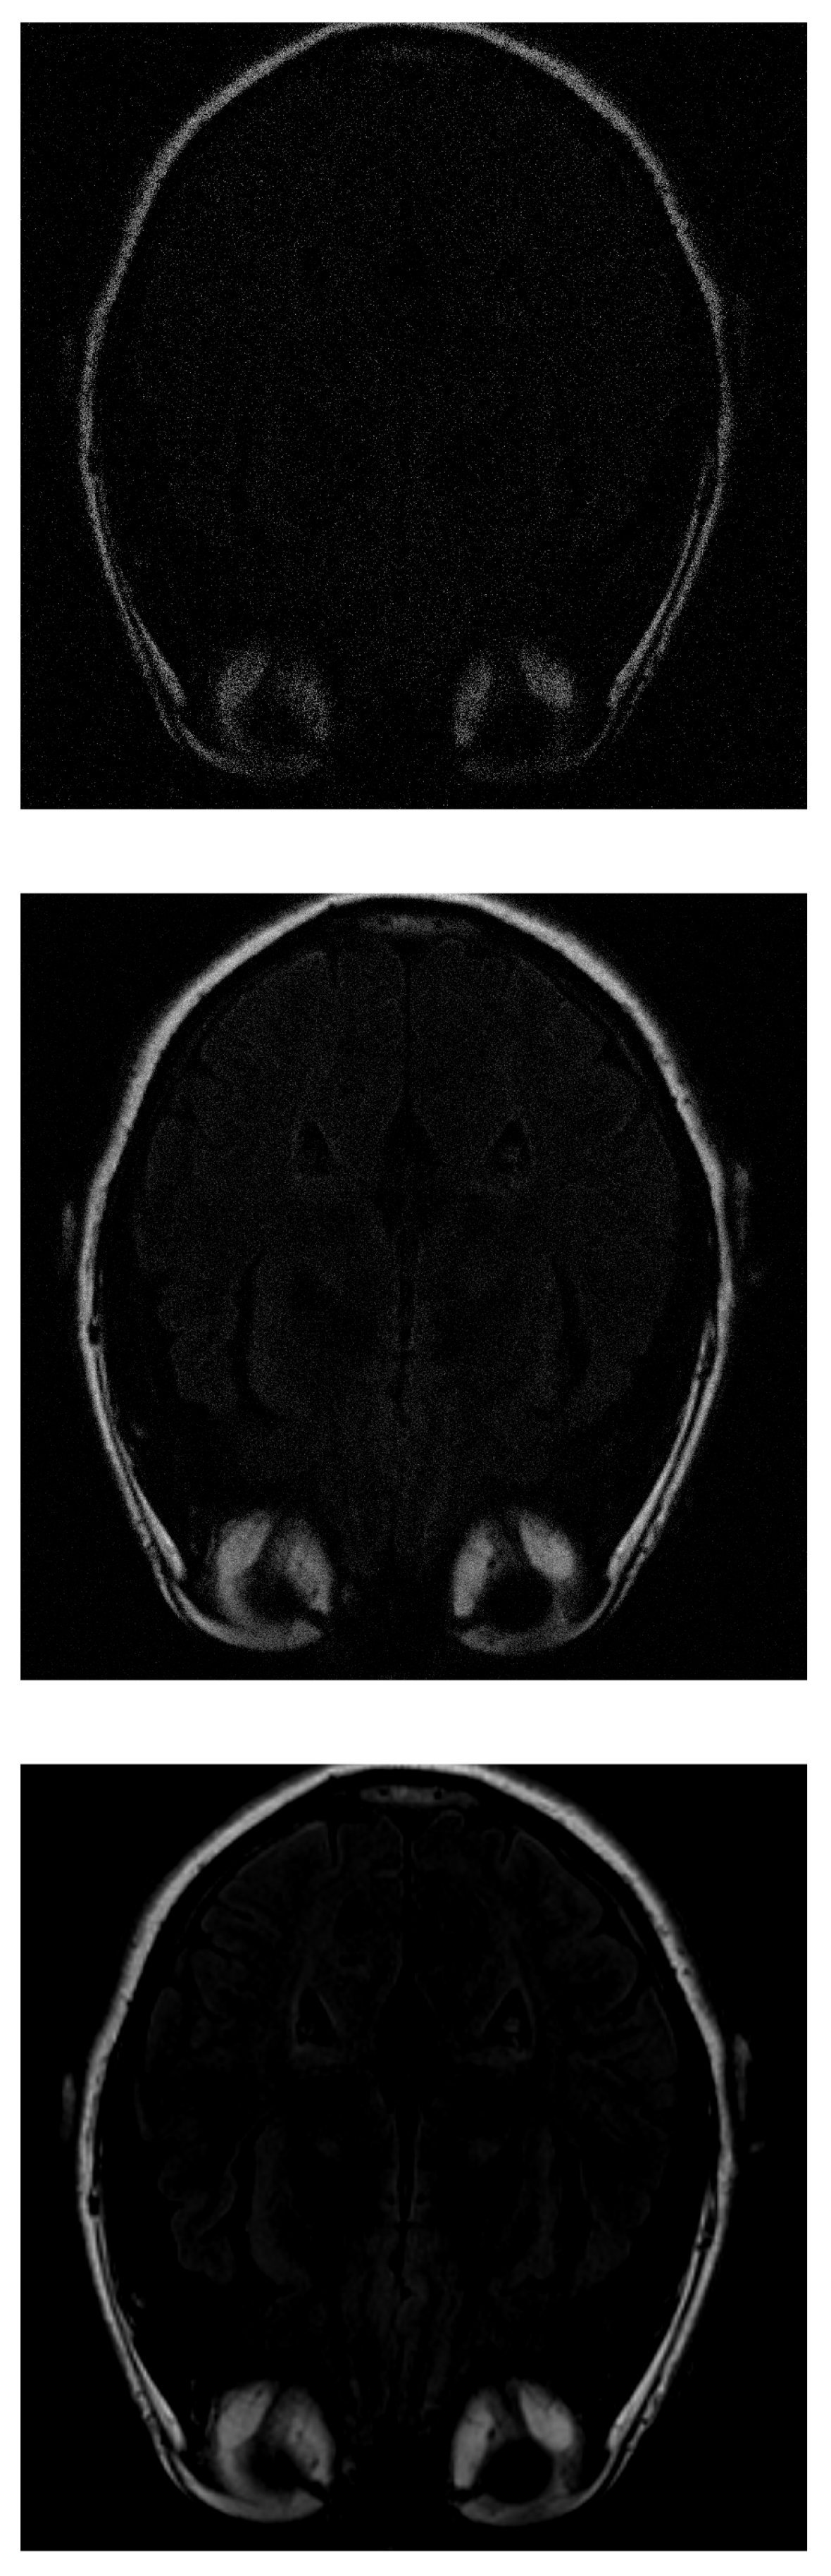

If IHTA is used for the reconstruction, more noise is detected on the inside of the head (where the white matter should be) with 30% of the initial signal values (Figure 7 top). With 70% of measurements (Figure 7 middle), an image similar to the same case was obtained with ISTA, but the target has more intense signals, which allows to distinguish better. The resolution increases as more data are added. However, when 100% of the data is reached (Figure 7 bottom), the white matter is not detected, it appears black.

Figure 7.

Reconstruction of the image in Figure 3 using IHTA with (top), (middle) and (bottom) of taken measurements.